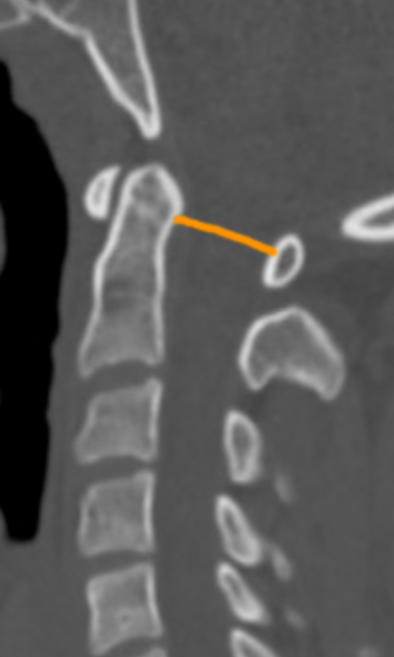

PADI represents the functional spinal canal diameter at the C1–C2 level. It directly estimates the space available for the spinal cord and is a strong predictor of neurologic risk.

• On sagittal CT, identify:

• The posterior surface of the dens

• The anterior surface of the posterior arch of C1

• Measure the minimal distance between these two points.